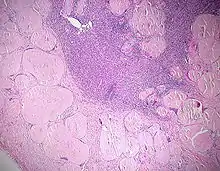

![]() Melanom-Metastase im Lymphknoten. |